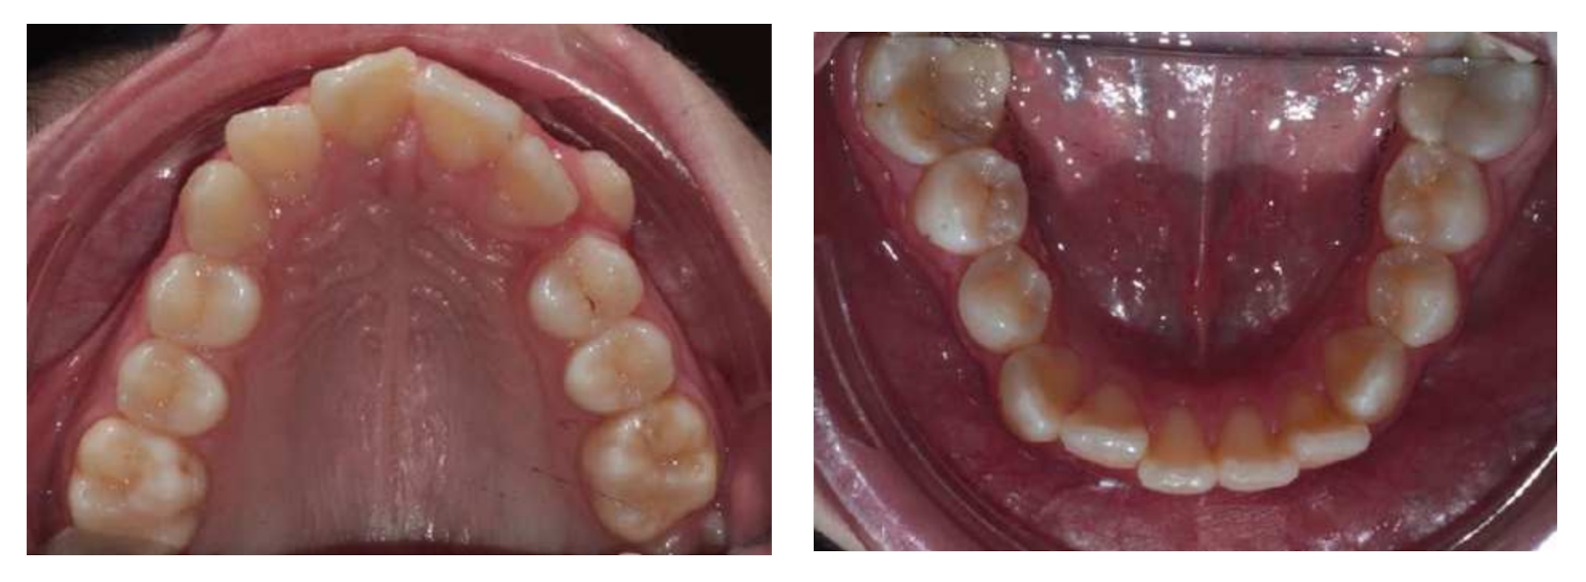

2. Diagnosis and Etiology

5. Treatment Progress

6. Treatment Results